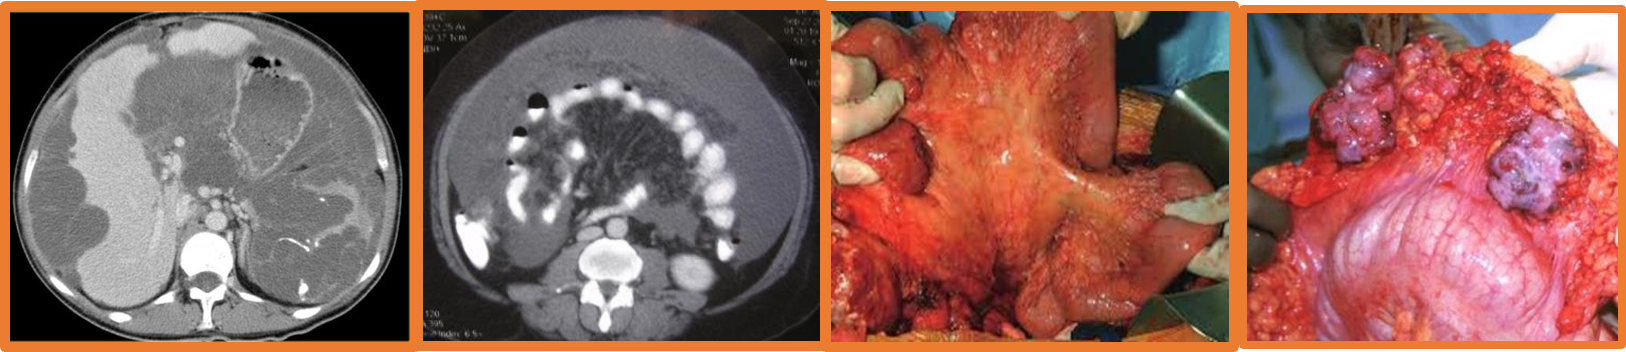

- Mesothelioma

- Exposure to asbestos

- Poor prognosis

- Abdominal pain, wt. loss. mass

- US, CT

- Debulking surgery,

- Chemo/radiotherapy

Carcinomatosis peritonei: Terminal event, studded with secondary growth, ascites (straw, blood stained).

- Rare, commoner in female due to ruptured mucinous cystadenocarcinoma (appendiceal origin in most cases).

- Abdominal distended due to yellow jelly like fluid.

- U/S, CT- scalloped indentation help diagnosis.

- Treatment: Excision of primary, debulking, chemotherapy.